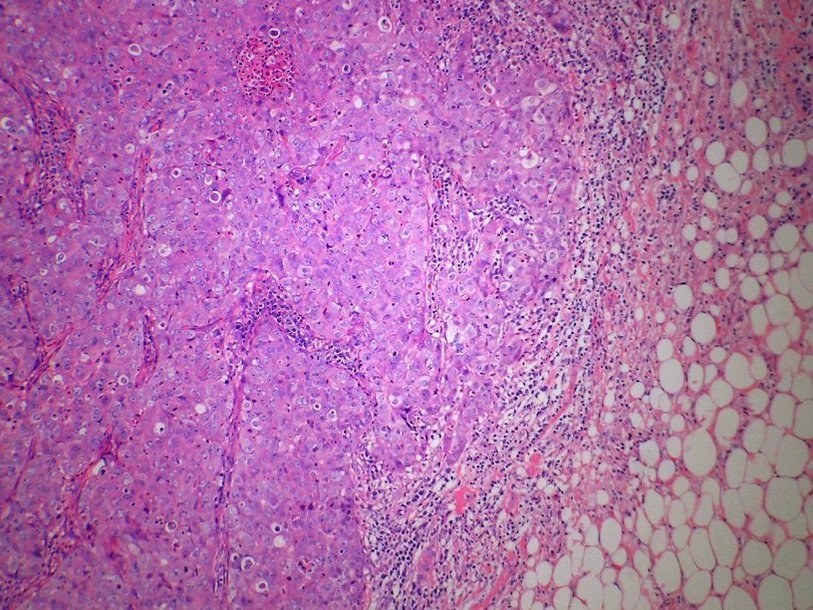

Клетки карциномы молочной железы Wikimedia Commons Еще советским алкоголикам был известен препарат «Антабус», с помощью которого пытаются с большим или меньшим успехом лечить алкогольную зависимость. В ходе применения этого препарата было замечено, что он проявляет противоопухолевые свойства. И лишь сейчас стал ясен механизм его воздействия на опухоль.